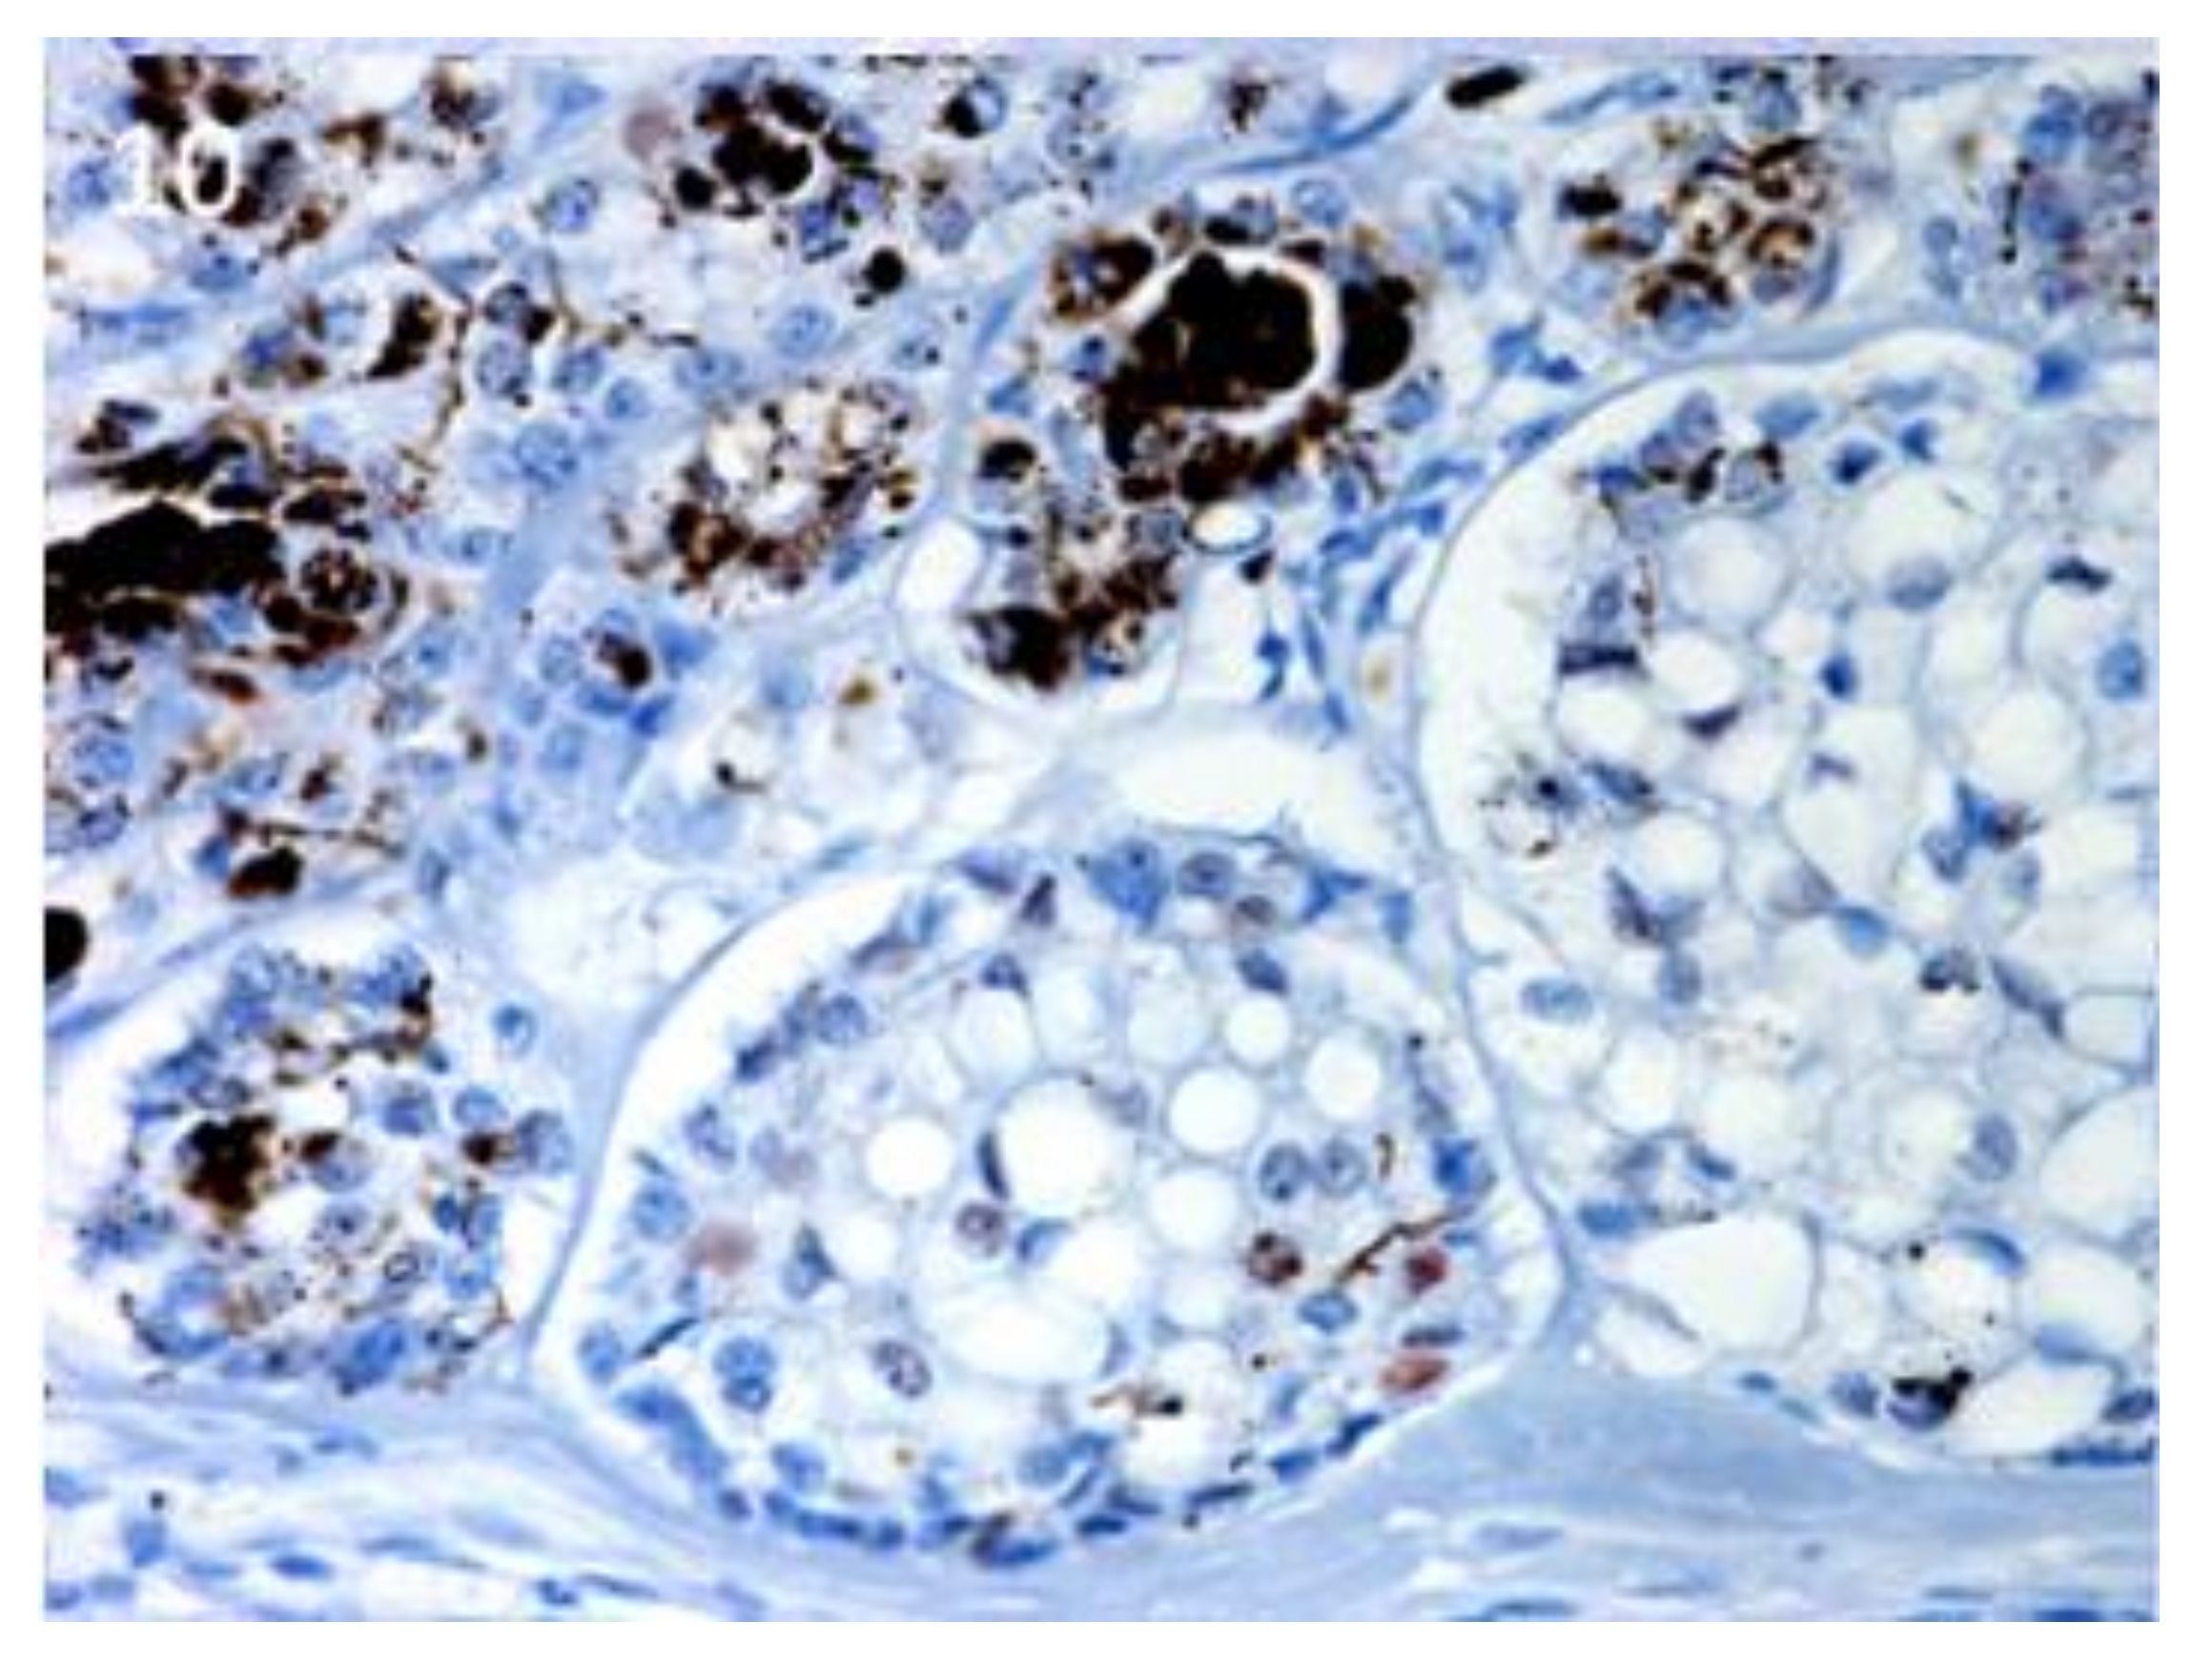

Figure 10.

TL, inferior type: scattered, positive nuclei evident in the neoplastic islands. Magnification 40×.